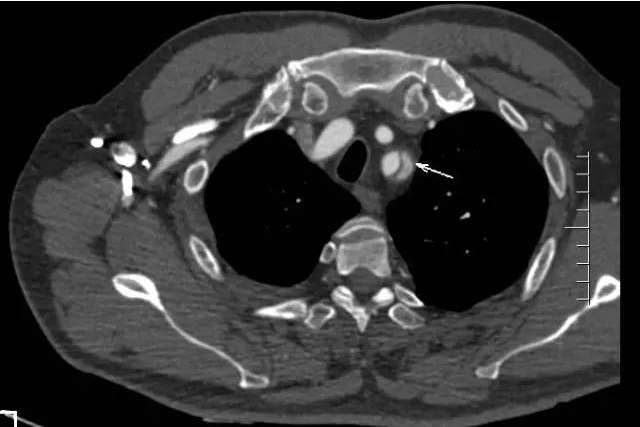

如此凶险的疾病,治疗就是跟时间赛跑。通过CT室开通的绿色通道,20分钟内即完成胸腹主动脉联合CTA检查。结果支持崔文军副主任医师的诊断,但糟糕的是这个病人的主动脉破口紧贴左侧锁骨下动脉,向上累及主动脉弓及升主动脉,向下一直撕裂至双侧髂动脉,右侧肾动脉闭塞,左侧肾动脉真假腔供血,存在急性肾功能衰竭及下肢缺血坏死风险!

左侧锁骨下动脉夹层(白箭头)